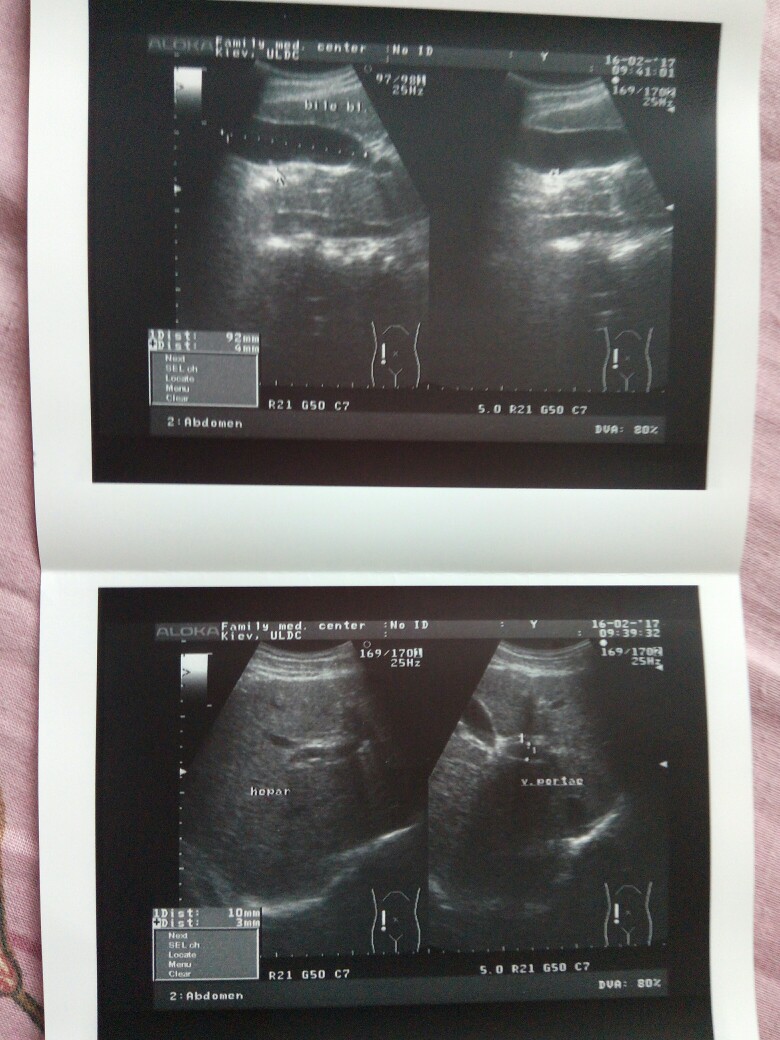

Сегодня забрала опись узи, сплошная печаль

Вложения

IMG_20170223_133333-780x1040.jpg

IMG_20170223_132125-780x1040.jpg

IMG_20170223_132050-602x640.jpg